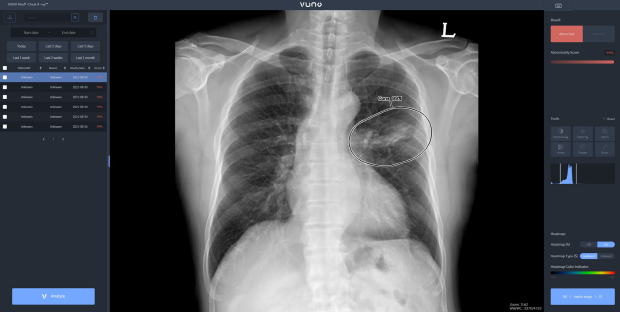

뷰노는 의료 진단용 엑스레이 시스템 전문 기업 디알젬(대표 박정병)과 인공지능 솔루션 기본 탑재 공급 계약을 체결했다고 19일 밝혔다.

이번 계약으로 뷰노는 AI 기반 흉부 엑스레이 판독 보조 솔루션 뷰노메드 체스트 엑스레이™를 디알젬에 공급한다. 디알젬은 전체 엑스레이 장비 라인업에 뷰노의 AI 솔루션을 기본 탑재해 국내 및 해외 주요 국가에 판매할 예정이다.

계약에 따라 양사는 AI 솔루션이 기본 탑재된 엑스레이 장비를 북미와 유럽, 중동 등 기존 디알젬의 글로벌 네트워크를 활용해 판매할 방침이다. 솔루션이 탑재된 제품은 엑스레이 촬영과 동시에 AI로 분석된 결과를 한 번에 쉽게 확인할 수 있어 AI 활용 경험이 없는 국내외 신규 고객의 유입이 활발할 것으로 기대된다.

한편, 뷰노메드 체스트 엑스레이™는 흉부 X-ray 영상에서 결절, 경화, 간질성 음영, 흉수, 기흉 등 주요 이상소견을 높은 정확도로 탐지하는 인공지능 솔루션이다. 의료진에게 이상소견의 소견명과 위치를 제시해 결핵, 폐렴 등 주요 폐 질환 진단을 돕는다. 경량화된 모델로 개발돼 다양한 X-ray 장비에 쉽게 연동할 수 있다.